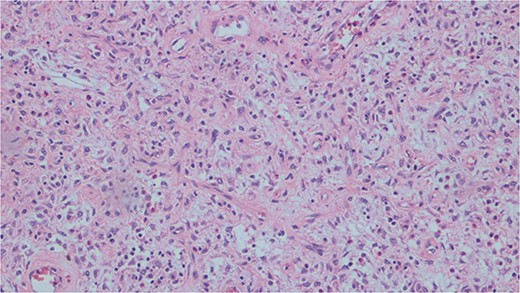

Histopathological analysis of the excised bowel segment revealed a low-grade, mural based spindle cell neoplasm (Fig. 5) with surrounding benign, reactive lymphadenopathy. The sample was sent for further immunohistochemical analysis for definite subtyping which demonstrated that the lesional cells stained positive for Vimentin, SMA and CD34. Desmin, S100, cytokeratin DOG-1, C-KIT, and ALK-1 were negative (Fig. 6). These findings were consistent with IFP in terms of morphology and immunohistochemical profile.

Histopathological slide demonstrating bland mesenchymal cells with a rich eosinophilic infiltrate.